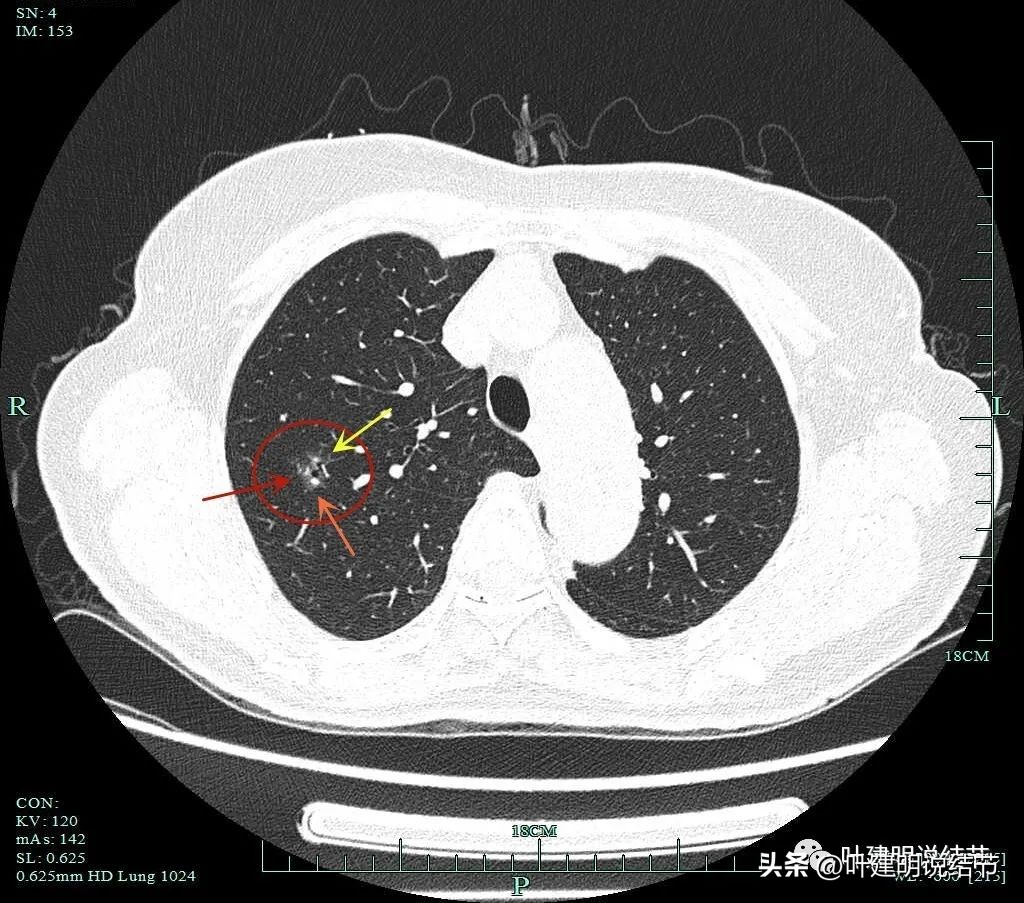

薄层显示病灶磨玻璃密度,内部有血管穿行,灶内有小空泡的样子,整体边缘轮廓较清。

灶内穿行的血管有异常增粗,且显得毛糙。灶内空泡样征是扩张的细支气管;表面不平,似有浅分叶的样子。磨玻璃部分密度较低。

上图显示血管进入病灶,进入后似乎就散掉了。